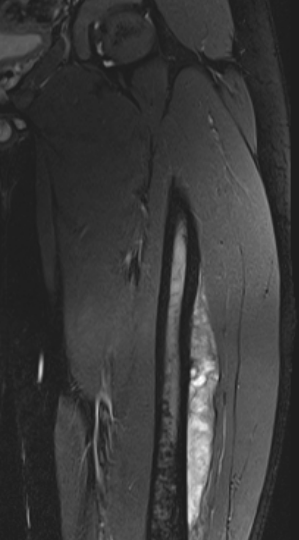

MRI

Low signal intensity of T1 / high signal intensity on T2

- intramedullary extent

- skip lesions

Significant soft tissue mass with significant edema

Pathological fracture with skip lesion

Ewing's femoral diaphysis, subtle on xray with large soft tissue component